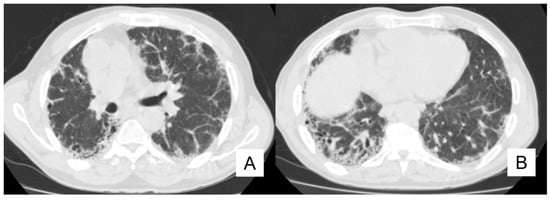

4.5. Pulmonary Infection